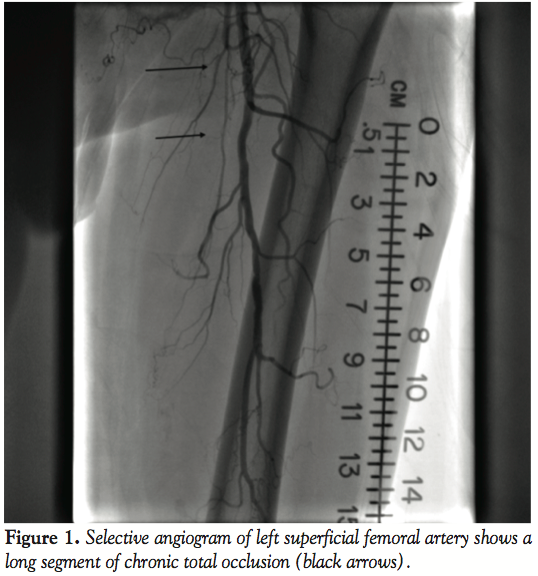

& Associates) was deployed and postdilated by a 6.0 mm x 40 cm balloon at nominal pressure at 9 atm. There was a persistent leak at the distal part of the aneurysm, so another 7.0 mm x 5 cm Viabahn stent was placed and again postdilated by a 6.0 mm x 40 mm compliant balloon at nominal pressure. Final angiogram showed successful exclusion of the pseudoaneurysm (Figure 5) and the patient tolerated the procedure well with no complications. One week later, the patient again presented to the hospital for worsening pain in his left thigh. Repeat CT angiography showed patent stent grafts with resolution of pseudoaneurysm. The patient’s symptoms improved by using a lidocaine patch and ibuprofen with no new symptoms in the 6 months follow-up.